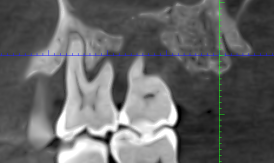

El CBCT permite una visualización tridimensional del hueso, aportando información clave que no se obtiene con estudios 2D:

- Evaluación precisa de la altura y volumen óseo alrededor de cada diente.

- Identificación de defectos óseos verticales y horizontales.

- Análisis de pérdida ósea en caras vestibulares y linguales.

- Valoración de furcaciones en molares.

- Detección de zonas con riesgo de movilidad o pérdida dental.

Esta información resulta esencial para establecer un diagnóstico periodontal realista y planificar el tratamiento adecuado.